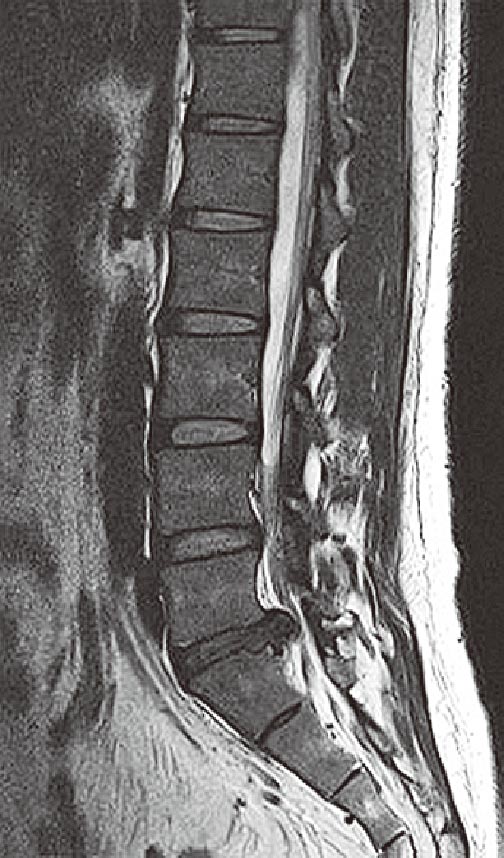

腰部MRIを下に示す.

この画像で認められるのはどれか.

- 1.骨粗鬆症

- 2.腰椎圧迫骨折

- 3.腰椎すべり症

- 4.後縦靱帯骨化症

- 5.椎間板ヘルニア

解答: 5